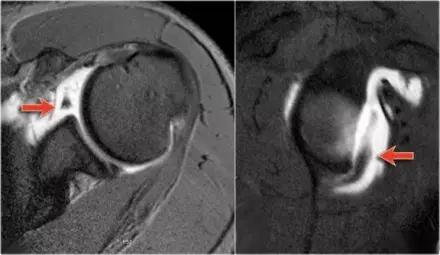

Hill-Sachs 损伤的 MR 片(来源:Hill-Sachs Injuries of the Shoulder)

MRI 示反 Hill-Sachs 损伤程度 (来源:Anatomical Reconstruction of Reverse Hill-Sachs Lesions Using the Underpinning Technique. Orthopedics May 2012 - Volume 35 · Issue 5: e752-e757)